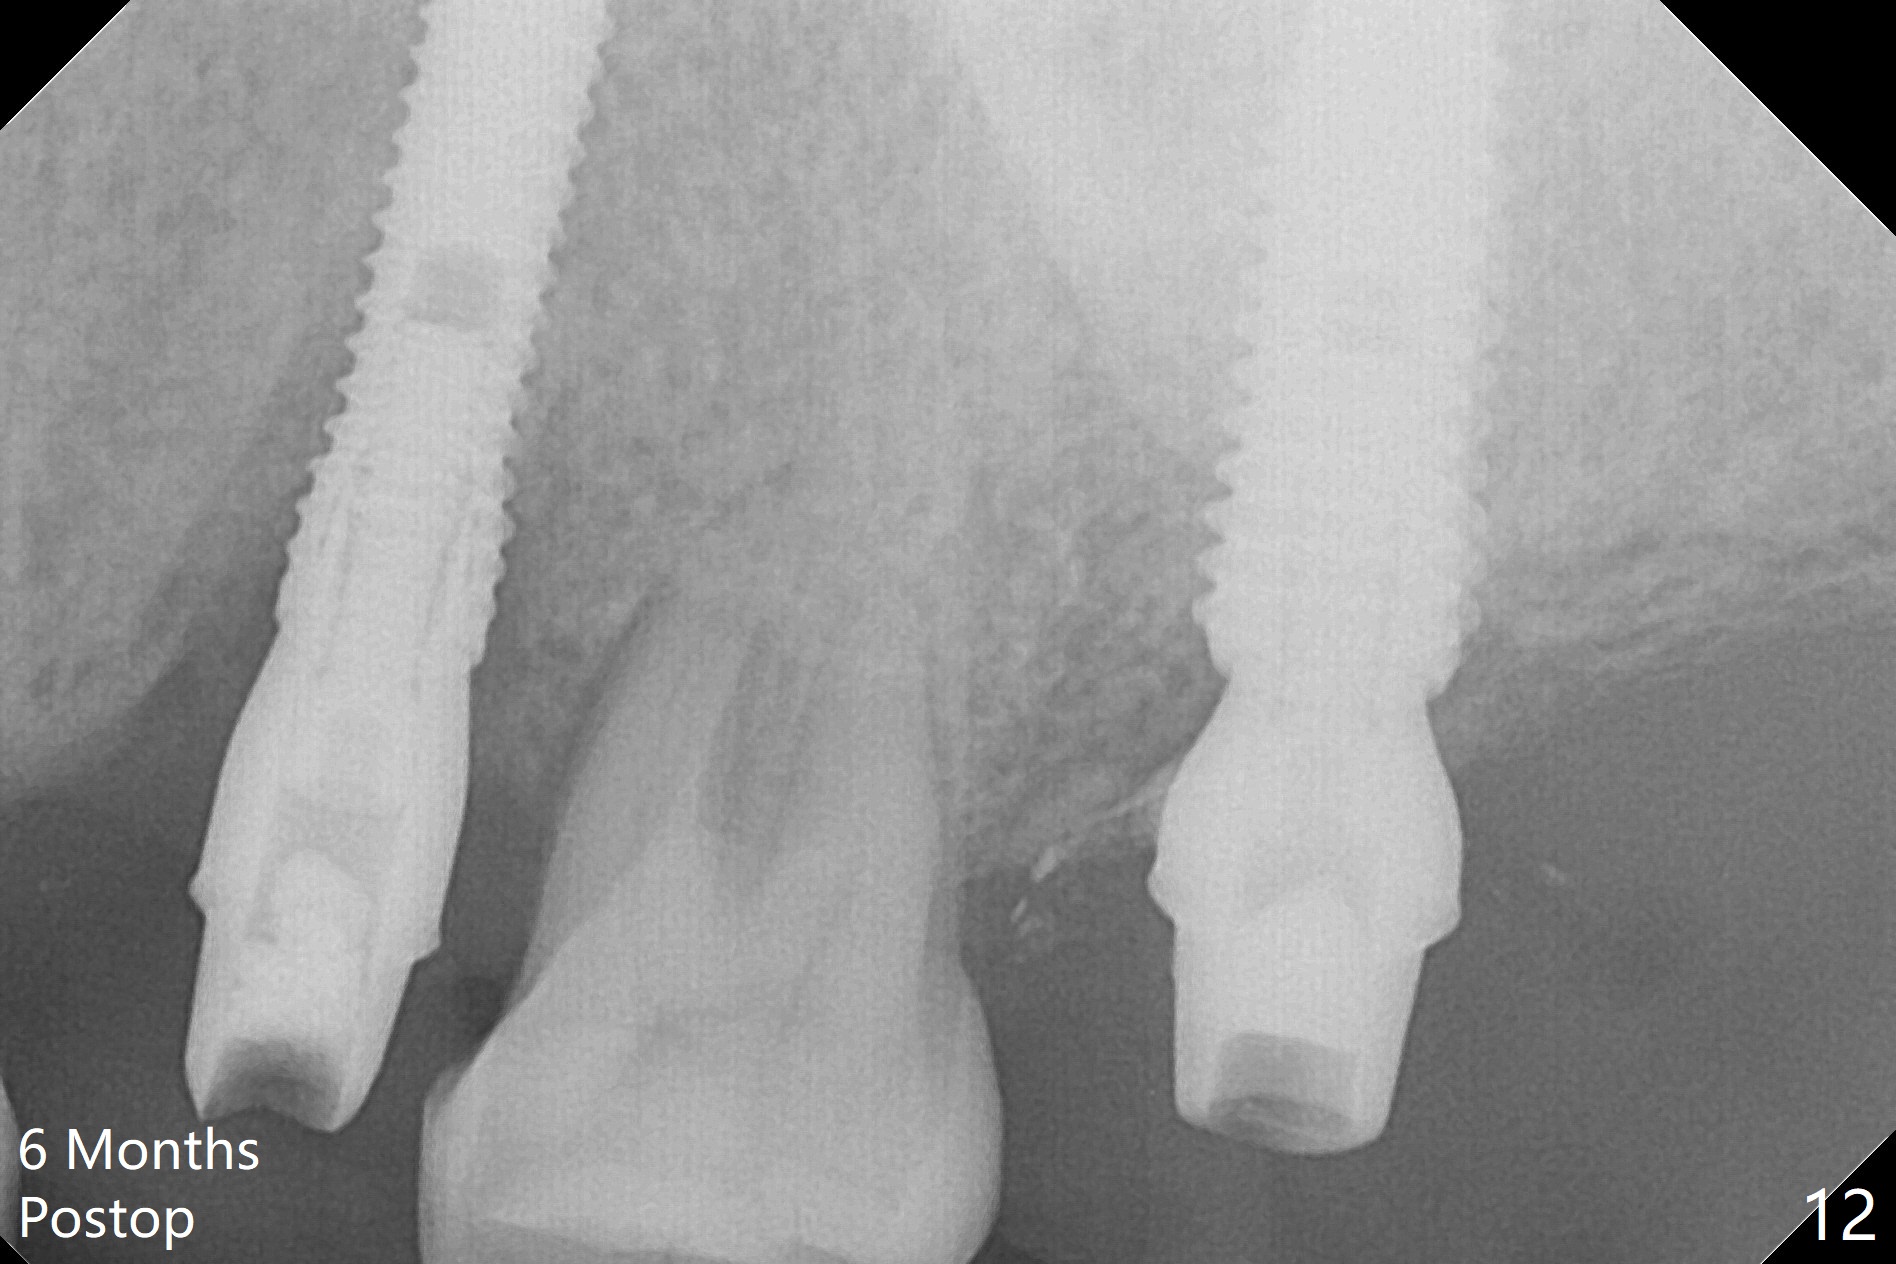

Initial osteotomy depth is 18 mm (Fig.1 green line) with 9 mm in the native bone (red line).  The bone density feels to be low.  There is at least 2 more mm bone apically (pink line).  The depth is increased by 2 mm so that when a 3.8x15 mm implant is placed, there is 10-11 mm implant/bone contact (Fig.2 red line).  There is large bony defect (Fig.3 *), which is bone grafted (Fig.4 *).  Finally a longer abutment is placed (4.5x5.5(5) in Fig.4 vs. 4.5x4(5) in Fig.2,3).  The 5 mm cuff does not look too long buccally (Fig.5) or palatally (Fig.6).   To prevent postop buccal gingival overgrowth (2), the buccal margin of an immediate provisional is subgingival (Fig.7-9 *).  Bone density between #13 and 14 appears to increase 3 months postop (Fig.10).  The implant seems to be equi-crestal (Fig.11 ^).  There seems to be more bone growth (i.e., decreasing gap) 6 months postop (Fig.12).  Impression is taken.  A crown is delivered nearly 7 months postop (08/07/2017).   While there is minimal bone loss at #13 and 15 three years and 4 months post cementation, the tooth #14 and 18 are mobile (Fig.13,14).